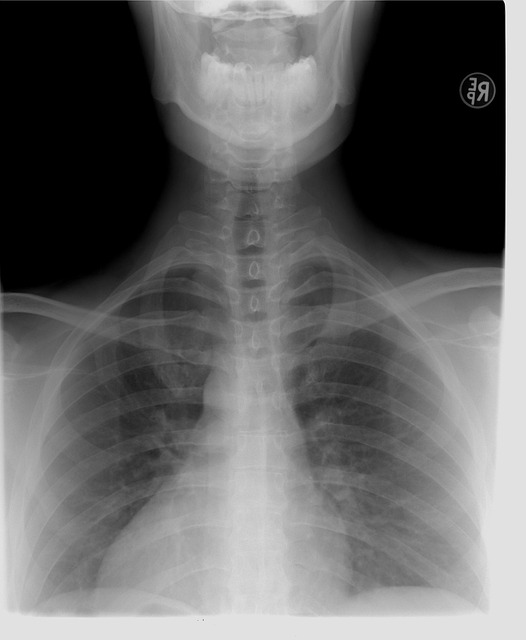

아기가 "컹~컹~"하고 개 짖는 것과 같은 소리를 낸다면 급성 폐쇄성 후두염을 의심할 수 있습니다. 급성폐쇄성 후두염은 목과 두 개의 성대 사이에 있는 후두 부위에서 발생하는 염증성 질환입니다. 심한 호흡곤란을 유발할 수 있고, 산소 공급이 제한될 경우 생명이 위협받을 수 있기 때문에 반드시 적절한 대처가 필요합니다. 이제 급성폐쇄성 후두염에 대해 더 자세히 알아보겠습니다.

일반적으로 3세~7세의 소아들이 급성폐쇄성 후두염에 잘 걸린다고 알려져 있습니다. 영유아들은 호흡기관이 아직 발달하지 않았기 때문에 감염에 취약하기 때문입니다.